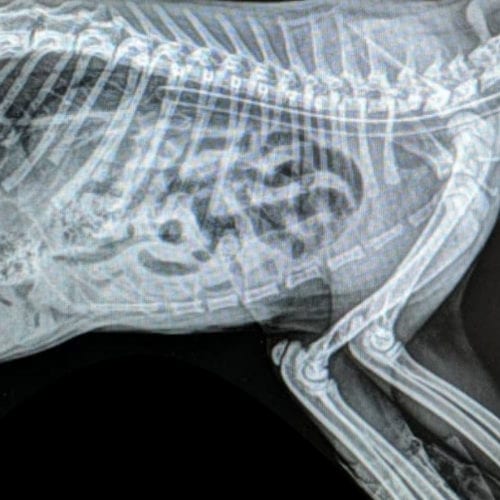

The pound transferred her immediately to Lort Smith, where we diagnosed her with congenital lymphedema — a malformation of the lymphatic system. Unfortunately, there is no cure for this condition, but we were determined to give this sweet little puppy the best chance at a normal pain-free life.

As with humans, acupuncture in animals is used to help the body heal itself by correcting energy imbalances. The technique requires the insertion of fine needles into the dog’s body at specific acupuncture points, where nerves and blood vessels meet.